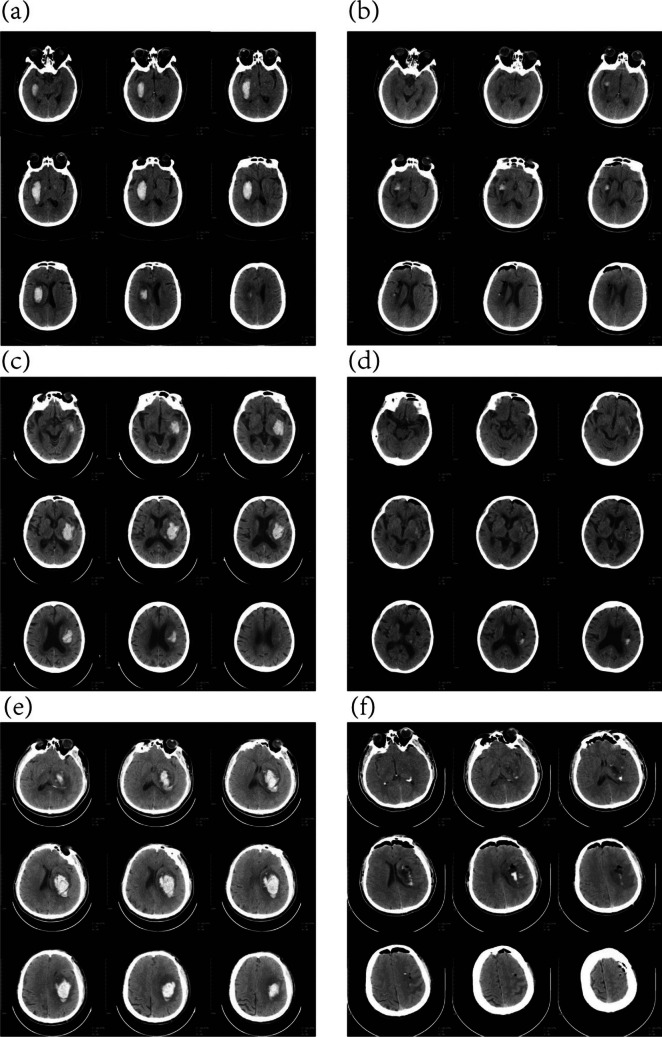

Abstract Image